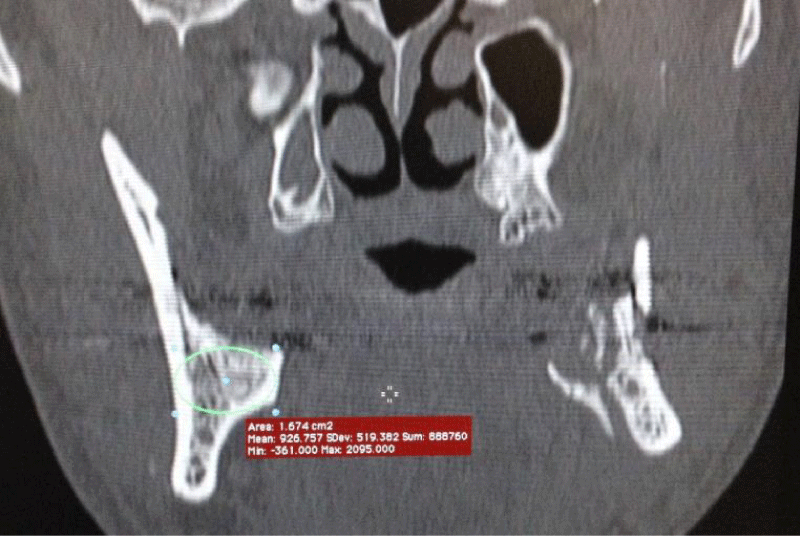

Figure 3:

CT 3D reconstruction showing D1–D2 bone density bilaterally.